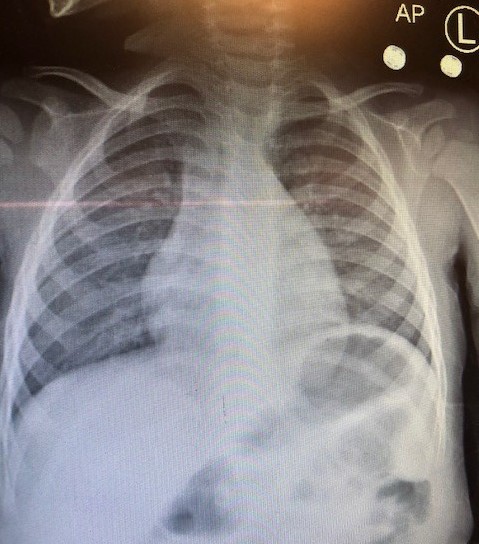

Laboratory tests. Results of a complete blood cell count showed a white blood cell count of 11,900/µL and a hemoglobin level of 11.0 g/dL. The lymphocyte count was elevated at 4300/µL, and the monocyte count was elevated at 1100/µL. Results of a rapid influenza antigen nasal swab test were negative. Chest radiography showed hyperinflated lungs and peribronchial cuffing (Figure). Blood culture results and urine culture results were normal. Urinalysis results were within normal limits, except for a ketone level of 40 mg/dL. Results of a rapid respiratory pathogen panel using polymerase chain reaction were positive for human metapneumovirus (HMPV) but negative for adenovirus, coronavirus, human enterovirus/rhinovirus, influenza, parainfluenza, and respiratory syncytial virus (RSV).

Figure. Chest radiograph showing hyperinflated lungs and peribronchial cuffing.